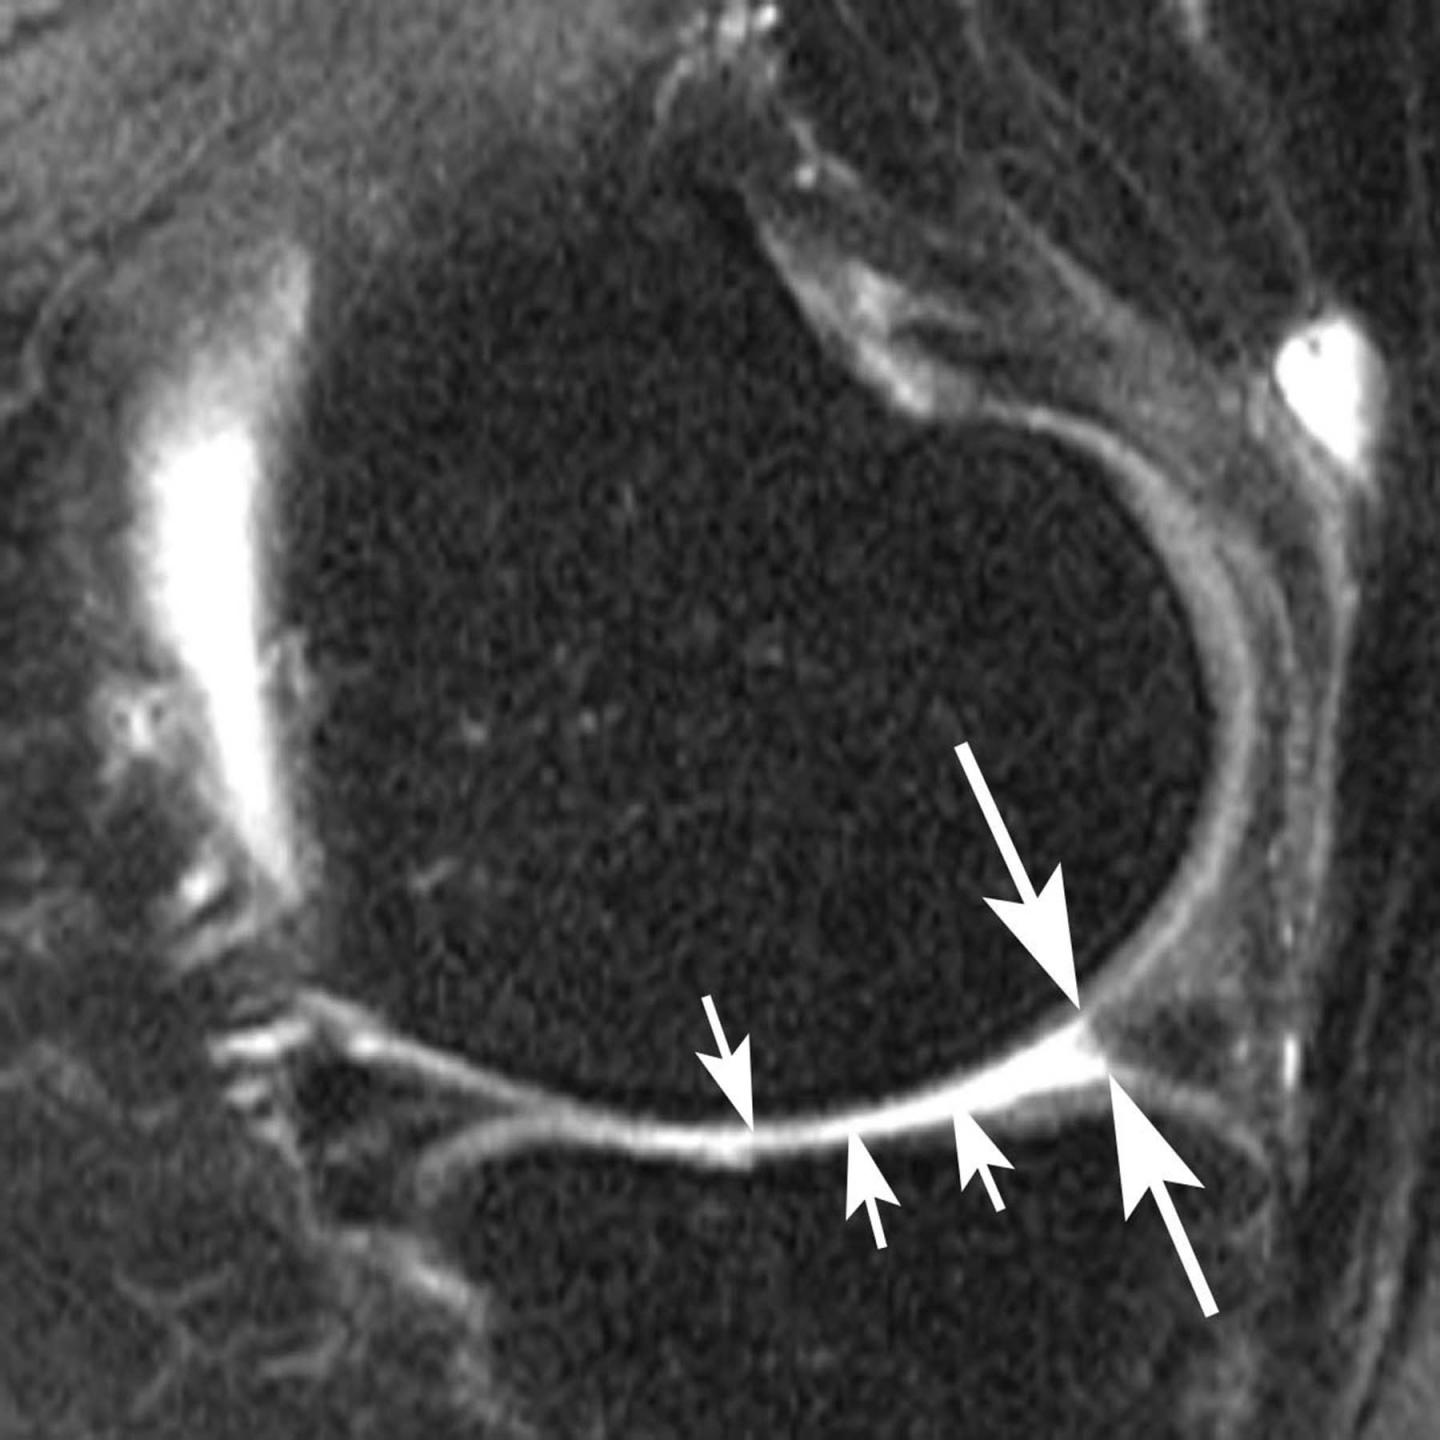

The new study focused on the meniscus, a wedge-shaped piece of cartilage in the knee that acts as a shock absorber between the femur, or thighbone, and tibia, or shinbone. The two menisci in each knee also play an important role in joint stability. Meniscal tears are among the most common knee injuries, and surgery is often performed to alleviate pain.

The researchers studied magnetic resonance imaging (MRI) exams of 355 knees that developed osteoarthritis during a five-year period, and a control group that was matched for age, gender, arthritic severity in both knees and BMI. Of all knees, 31 underwent meniscal surgery during the year prior to the arthritis diagnosis, and 280 knees had signs of meniscal damage on MRI but did not have surgery. Also part of the analysis were control cases with no meniscal damage. The researchers assessed the risk of developing arthritis and cartilage loss during the following year for the different groups.

"We found that patients without knee osteoarthritis who underwent meniscal surgery had a highly increased risk for developing osteoarthritis and cartilage loss in the following year compared to those that did not have surgery, regardless of presence or absence of a meniscal tear in the year before," Dr. Roemer said.

All 31 of the knees that underwent meniscal surgery during the prior year developed osteoarthritis, compared with 165 (59 percent) of the knees with meniscal damage that didn't have surgery. In addition, cartilage loss was much more common among knees that had undergone surgery: 80.8 percent of knees with surgery showed cartilage loss, compared with 39.5 percent of knees with meniscal damage and no surgery.